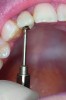

However, screw-retained restorations can still be placed when the trajectory and implant position are interfering with esthetic areas without compromising the final results (Figure 1). What is needed for this is excellent laboratory support and highly trained technicians who understand and can deliver this type of restoration.

In this case, a prefabricated stock abutment was used. The abutment was milled to the desired height and width based on a diagnostic full-contour wax-up of the desired final restoration. Proper space for the crown materials and a desirable path of draw was achieved during the milling process. Then, the screw access hole was tapped on the palatal aspect of the restoration (Figure 2 through Figure 4). This achieves both the desired esthetics as well as retrievability and elimination of any subgingival cement that may affect the soft tissue.

Figure 1. Implant fixture No. 7 facially inclined.

Figure 1

Figure 2. Access screw designed to engage on palatal aspect.

Figure 2

Figure 3. A 1-mm diameter screw used to retained crown.

Figure 3